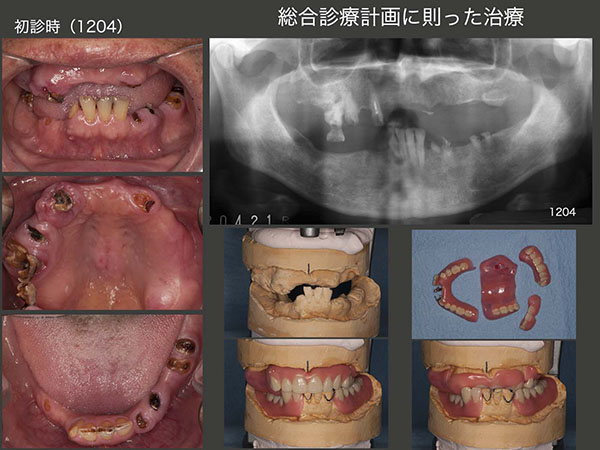

4.総合診療計画に則った治療

2012年4月初診,64歳男性.主訴は,義歯を製作して欲しい.子供の頃のトラウマがあり,25歳から1回も歯医者に通ったことがないとのこと.もちろん義歯を入れた経験はなく,柔らかい食べ物を顎堤で咬んでいたとのこと.

最初に拝見した時は,単純に義歯を製作すればよいだけと思ったが,暫間義歯の製作にあたって,どのように治療するか悩んでしまった.と言うのは,上顎右側の歯および下顎の前歯が挺出しており,義歯を装着するスペースが全くないことに気づいたからである.スライド中段に咬合器に模型を付着した状態を示すが,上顎前歯をいかに排列するか?から模索が始まった.なお,水平的下顎位の確認のためにゴシックアーチの記録を行った.また,このケースで抜去した歯は歯根の全くない左上3,左下3および右上6の頰側根のみである.

2012年8月に暫間義歯を装着した.結局上顎前歯は,義歯の安定を優先したことで,このような形に落ち着いた.上顎義歯に対する違和感はそれ程でもなく,このような義歯にもかかわらず,食事がとりやすくなったとおっしゃっていた.